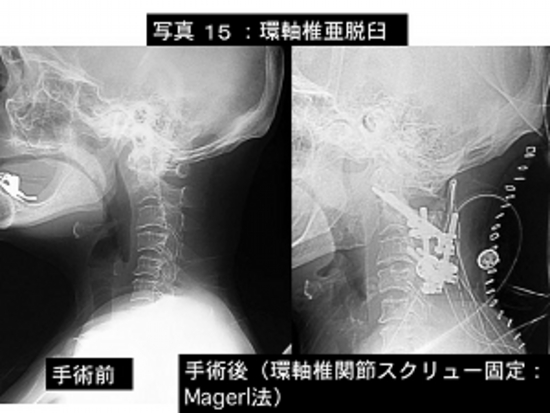

写真15:環軸椎亜脱臼といって、第1頚椎(環椎といいます)と第2頚椎(軸椎といいます)にずれが生じひどくなれば呼吸が止まることもある恐ろしい状態です。

左が手術前で右が手術後の単純レントゲン撮影像です。

おおきなねじで環椎と軸椎を強固に固定しています。

患者さんは手術後新たな症状なく歩いて退院されました。